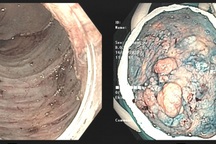

Ung thư trực tràng là ung thư phát triển trong các tế bào của trực tràng. Trực tràng nằm bên dưới đại tràng sigma và phía trên hậu môn. Trực tràng và ruột kết đều là một phần của hệ thống tiêu hóa, do đó, ung thư trực tràng và ruột kết thường được gọi chung là ung thư đại trực tràng.

Mới đầu, ung thư trực tràng có thể ảnh hưởng đến các mô lót trực tràng. Trong một số trường hợp, nó ảnh hưởng đến toàn bộ trực tràng. Sau đó, ung thư có thể lây lan đến các hạch bạch huyết hoặc các cơ quan lân cận, gan thường bị ảnh hưởng. Các khu vực di căn khác có thể bao gồm: bụng, não, phổi, buồng trứng.